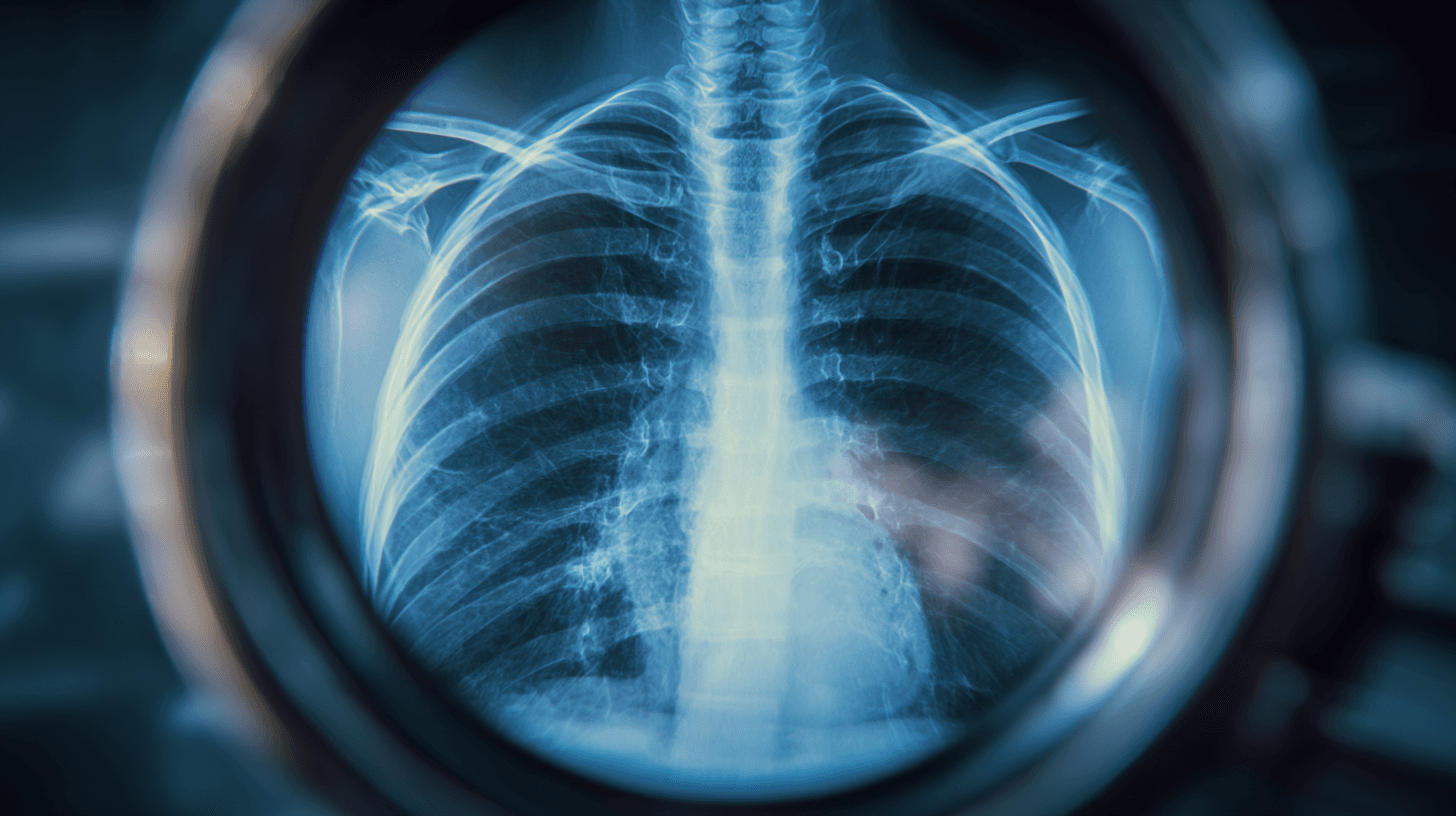

흉부 X-ray 기반 골다공증 선별의 의미

특히 흉부 X-ray는 기회기반 스크리닝에 가장 적합한 영상입니다.

촬영 빈도가 높고

방사선 노출이 적으며

대부분의 병원에 장비가 있고

디지털화가 이미 잘 되어 있습니다.

프로메디우스의 골다공증 선별 AI는 이 흉부 X-ray를 활용해 골다공증 위험 신호를 조기에 포착하는 것을 목표로 합니다.

중요한 점은, 이 기술이 진단을 대신하지 않는다는 것입니다. 역할은 명확합니다.

"이 환자는 골다공증 가능성이 높아 추가 평가가 필요하다."

"지금이 바로 DXA 검사를 고려해볼 시점이다."

즉, 골절이 발생하기 전, 위험군 선별(screening)의 역할입니다.

흉부 X-ray 한 장, 이미 찍혀 있는 영상 하나가 누군가의 골절을 막고, 삶의 질을 지킬 수 있다면 그 기회를 놓칠 이유는 없습니다.